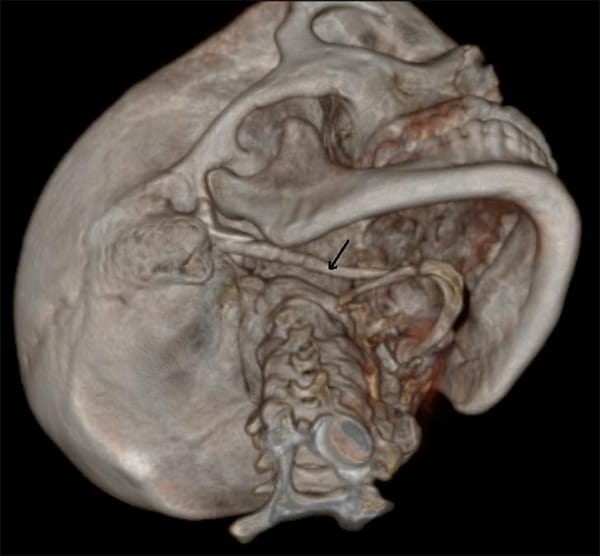

Eagle syndrome is a rare condition where the styloid process becomes elongated or the stylohyoid ligaments become calcified. When the process elongates, it can constrict nerves, the carotid artery, and create a variety of symptoms that are often misdiagnosed. (see Image 1 and 2)

Image courtesy Benutzer:MBq, via Wikimedia Commons.

Radiographic Imagery

Is the styloid process approximately 2.5cm, or has it elongated? How does the TMJ look? If the styloid process is elongated and the TMJ looks relatively normal, a referral to an ear, nose, and throat specialist (ENT) is advised.

The ideal radiologic review is with 3D computed tomography. However, many dental offices do not have this imagery available.4 The referral to an ENT for further examination should be recommended if a patient does not respond to TMD therapy, NSAIDs, or when radiographs do not reveal any significant temporal mandibular disorder (TMD) issues.